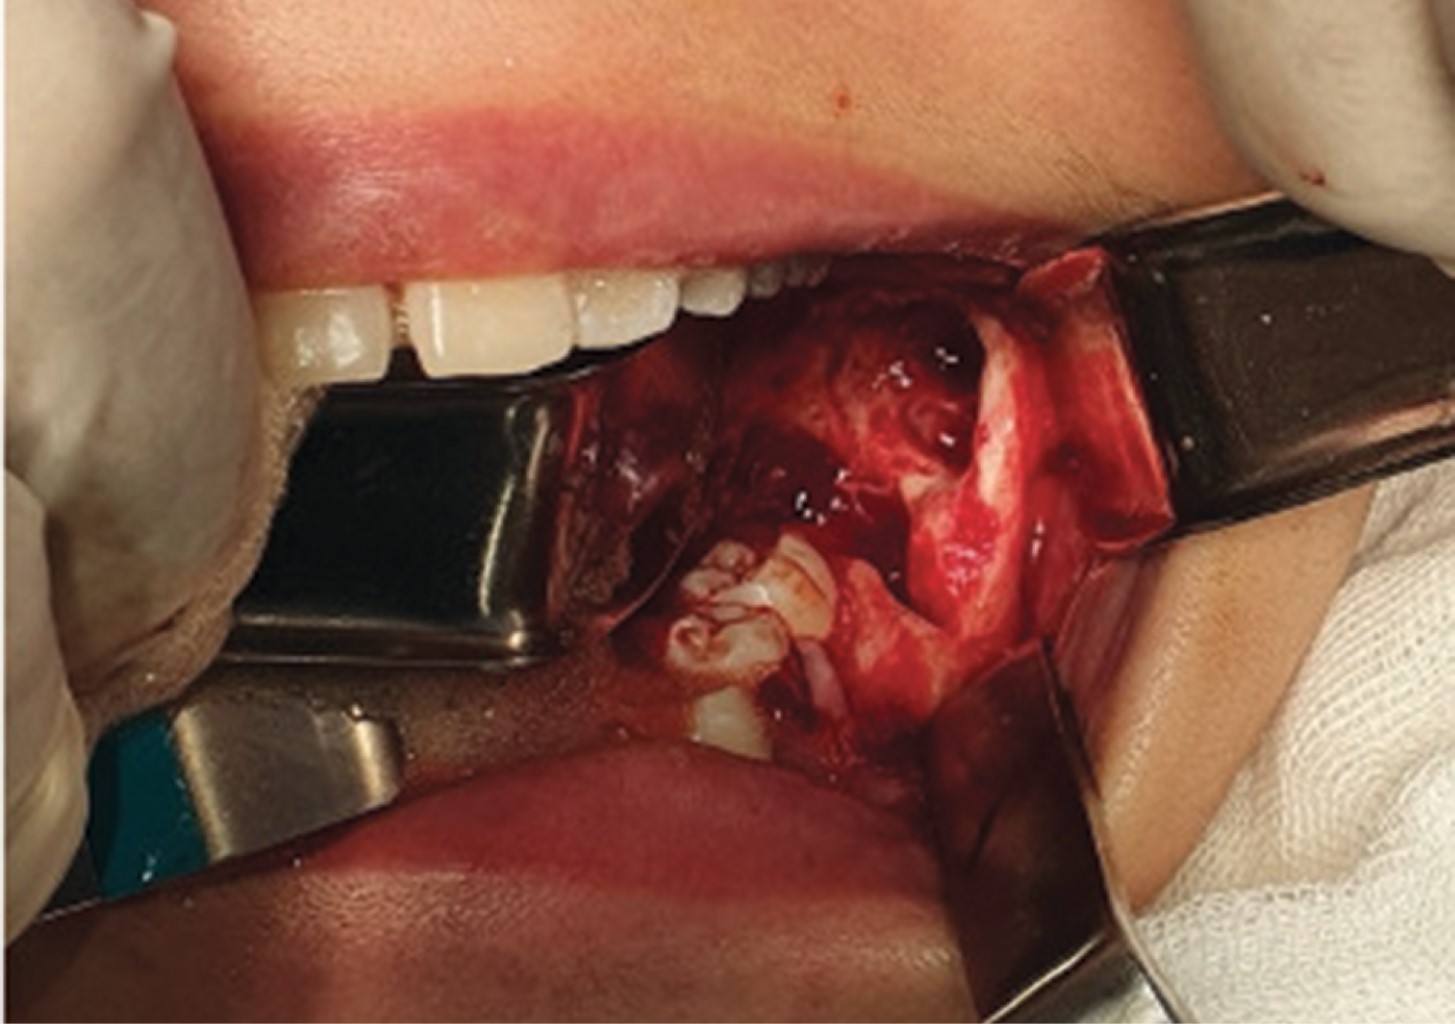

Bajo anestesia general y con intubación orotraqueal, se realizó la resección quirúrgica conservadora de la lesión, con curetaje en todo el lecho quirúrgico y odontectomía del segundo molar inferior izquierdo. No se observó comunicación al conducto dentario inferior ni perforación de las corticales óseas en el transoperatorio (Figura 3).

Se colocaron suturas en la periferia de la herida, simulando una marsupialización y se introdujo en el lecho quirúrgico injerto óseo y membrana para la correcta regeneración de tejidos y así obtener una mayor facilidad en la parte de rehabilitación con implante.